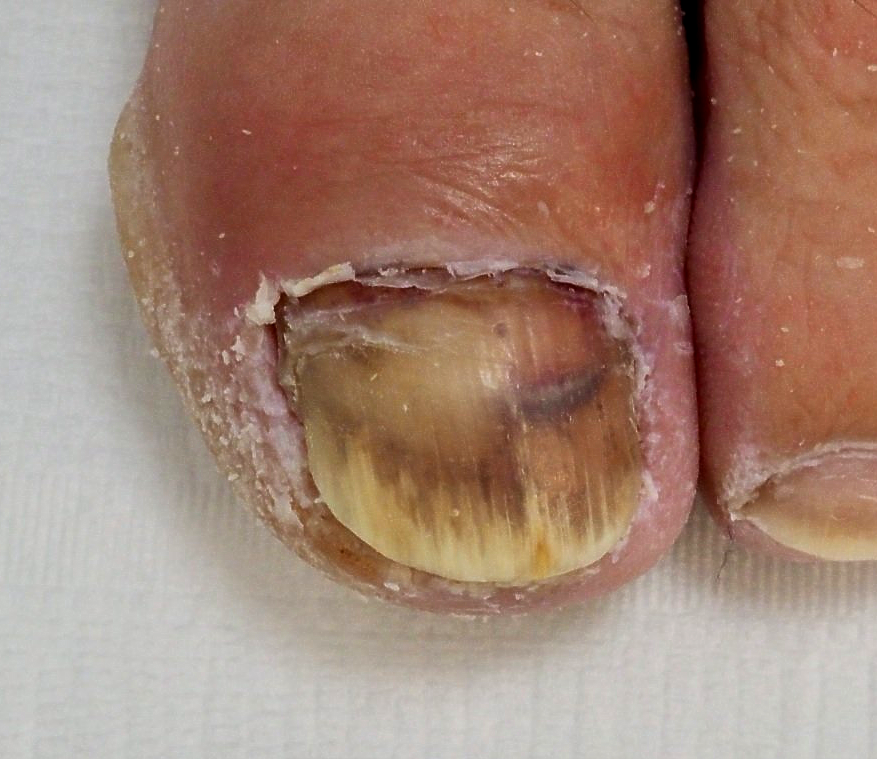

🔴Bild 3: der geborgene Nagelspan Bild 4: in dieser Position grub sich der Nagel durch das Gewebe